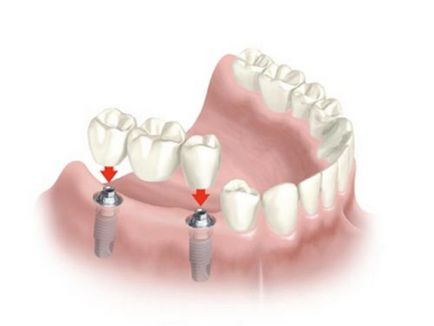

Напълно нов в зъбни протези между разработени и фиксирани структури - е фурнири, керамични инлеи, корони от циркониеви протезни мостове, без да се обръща зъбите и титанови импланти.

- брой комплекси ортопедични манипулации (завъртане зъбни импланти създаване получаване на смола);

Дъвченето отделя включва създаване на по-устойчив материал, такъв протеза се прави въз основа на имплантиране на имплант за закрепване, кукички или зъбни мостове.

Лепило мостове се състоят от един зъб с две дюзи, които специално лепило лепило плътно прикрепени към съседни зъби.

Това е най-нежен начин на протеза, тъй като тя не се нуждае от предварително повратна на зъбите.

Недостатъкът на този протеза - периода на носене не по-дълъг от пет години.